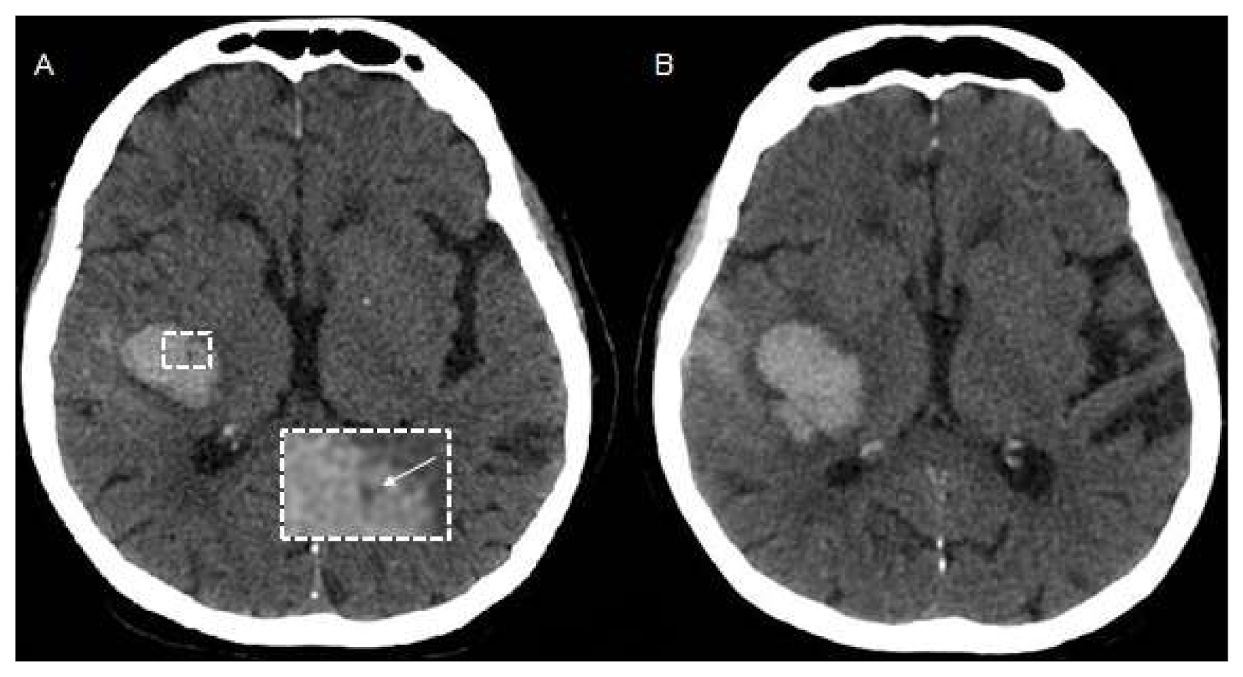

2. Imaging to Identify ICH Etiology

2.1. CTA and DSA for Macrovascular Causes

2.2. Value of CT-Perfusion

2.3. MRI